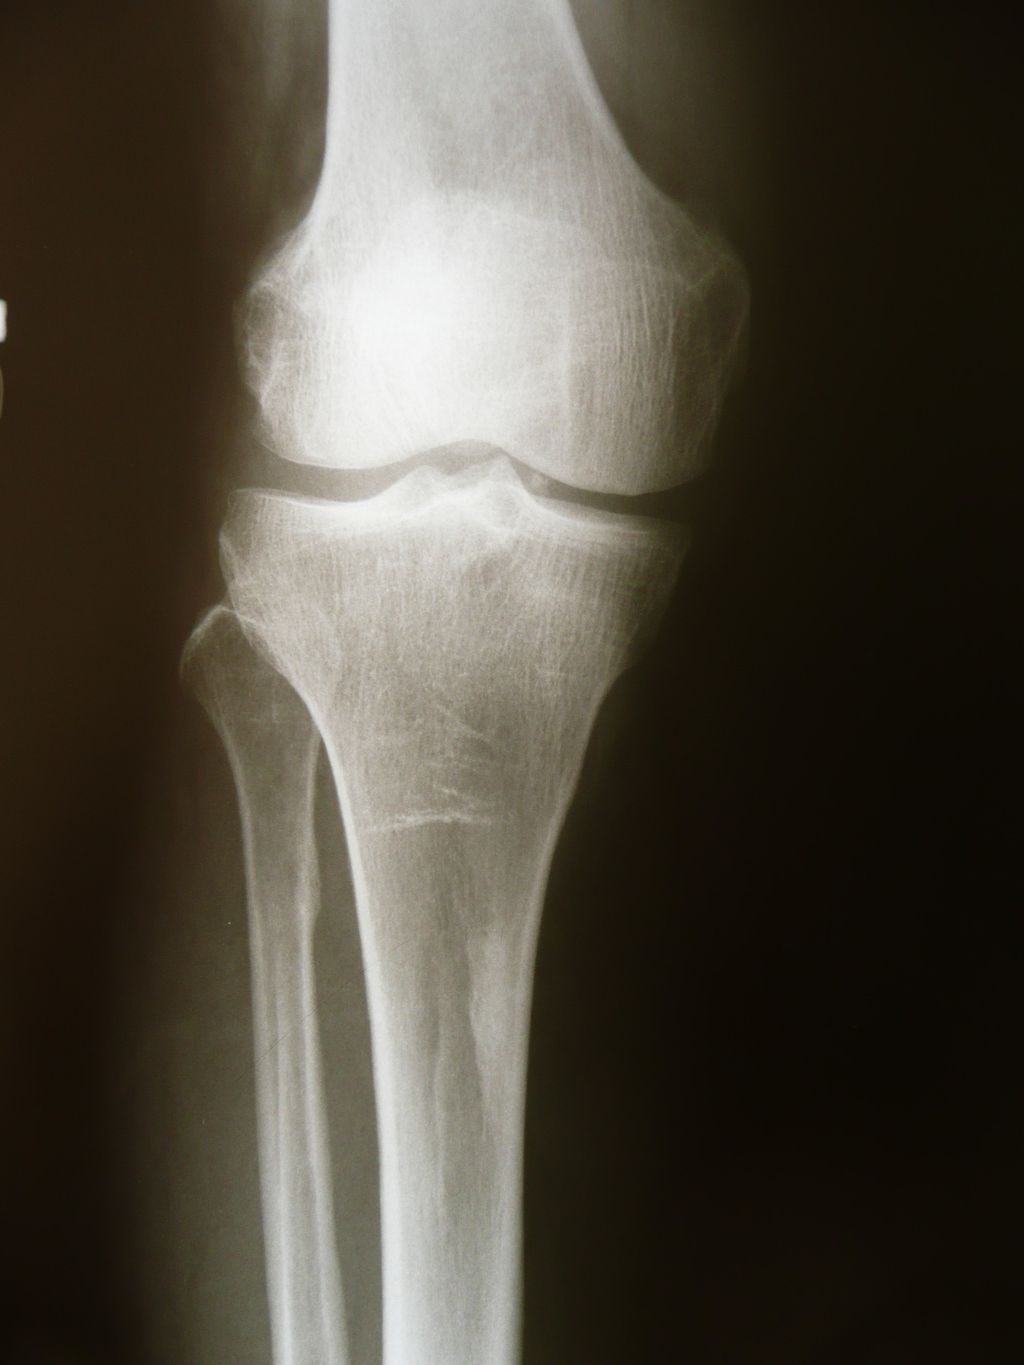

Diagnosis of Meniscus Injuries

![]()

Physical Examination

In our clinical practice, we place significant emphasis on the physical examination when assessing potential meniscus injuries. This step is crucial as it allows us to evaluate the knee’s range of motion, stability, and the presence of any joint line tenderness, which can be indicative of a meniscus tear. We perform specific maneuvers, such as the McMurray test, where we rotate the knee while it is bent and then straighten it to check for pain or a clicking sound, which may suggest a tear.

We also assess for effusion, or swelling within the knee joint, which can be a sign of internal knee damage including meniscus injuries. It’s important to note that while these tests are valuable, they are not infallible. A lack of symptoms during these tests does not necessarily rule out a meniscus injury.

Tip: Always consider the patient’s history and symptomatology in conjunction with the physical examination findings to form a more accurate clinical picture.

Imaging Techniques

In our quest to accurately diagnose meniscus injuries, we often turn to imaging techniques. These methods provide us with a clear picture of the internal structures of the knee, allowing us to assess the extent of the injury. Magnetic Resonance Imaging (MRI) is the gold standard for visualizing meniscus tears due to its high sensitivity and specificity. However, we also consider other modalities such as ultrasound and X-rays, particularly when MRI is contraindicated or unavailable.

Ultrasound is advantageous for its real-time imaging capabilities, which can be particularly useful in dynamic assessments. X-rays, while not as detailed for soft tissue injuries, can help rule out other conditions such as fractures or osteoarthritis. It’s important to note that while imaging provides valuable information, it should be interpreted in conjunction with clinical findings.

Tip: Always correlate imaging results with physical examination findings to ensure a comprehensive assessment of the meniscus injury.